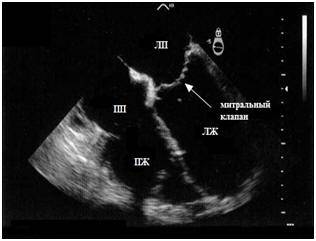

Сердце человека при эхокардиографическом обследовании (УЗИ сердца). Добавочная хорда представлена эхоплотным линейным образованием, которое можно просмотреть в двух плоскостях сечения, расположенным в полости левого желудочка (ЛЖ), ближе к митральному клапану.